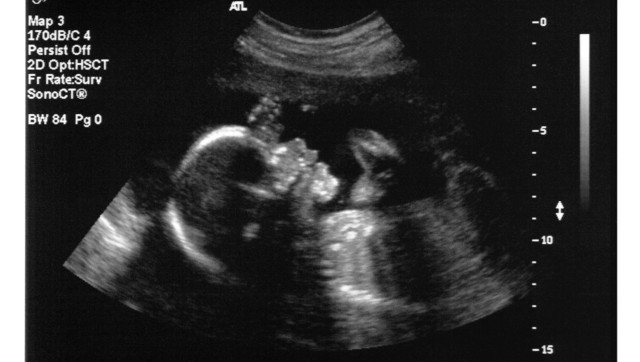

Catholic Health Initiatives, which runs St. Thomas More hospital in Cañon City, Colo., made headlines this week for its surprising line of defense against the lawsuit, which was filed husband of the women who was pregnant with unborn twins and in its care (the woman died with the babies in her womb). Catholic social teaching says that fetuses are people -- the argument is part of the church's strong pro-life and anti-abortion positions.